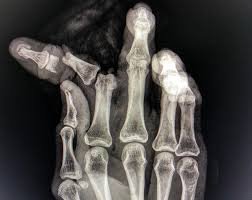

Crush Injuries

Trauma that compresses tissue, damaging not just skin but underlying muscle, blood vessels, and bone. The full extent of damage may not be immediately apparent, with tissue death developing over days.